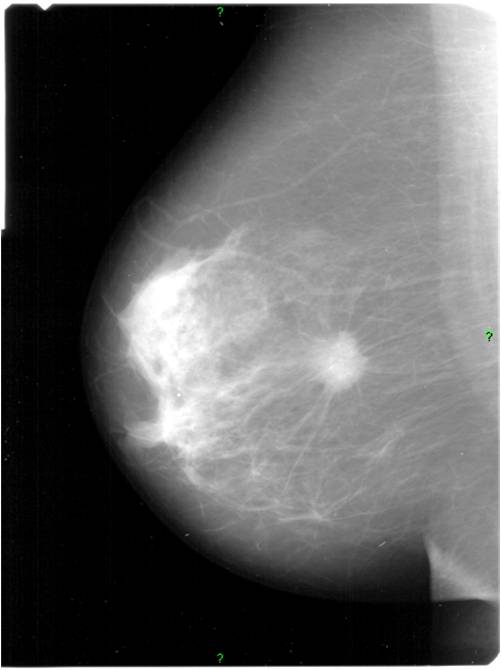

The soft-tissue lesions can appear as well-defined, rounded or oval shaped (Pictures 13.,14.) or as ill-defined, star-shaped masses (Picture 15.). Rounded or oval lesions are in most cases benign and their malignant proliferation is rare, they do not require surgical removal. These lesions are usually cysts and fibroadenomas, at other times hamartomas, lipomas and at very few times malignant tumors.

Star-shaped lesions are very typical of malignant tumors.

o “White star”: describes the tumor body with dense spiculations of various lengths appearing around the core = carcinoma

Image

Picture 13.

Picture 14.

Picture 15.